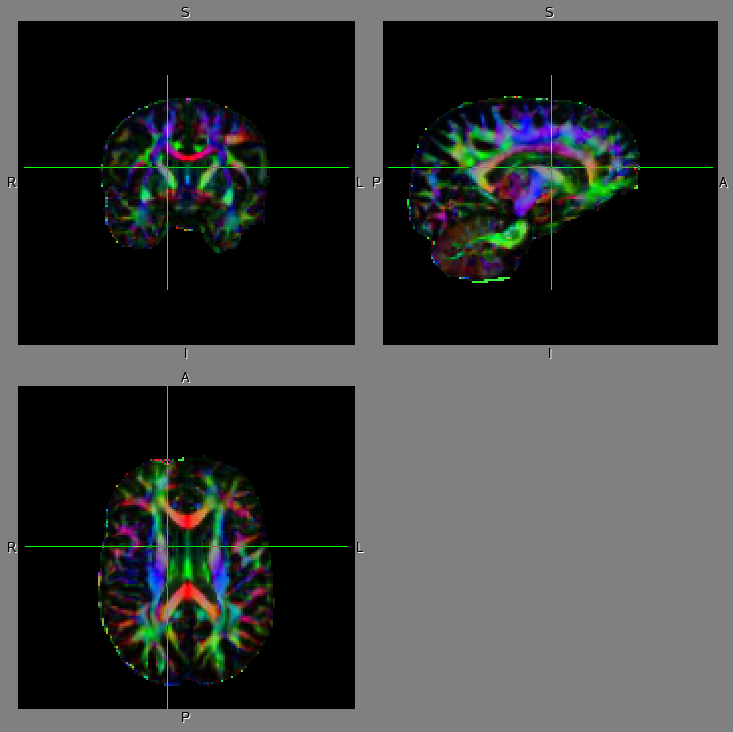

Outputsbvecs, bvals: vector file and b-value file. dti_FA, dti_L1, dti_L2, dti_L3, dti_V1, dti_V2, dti_V3, dti_MD, dti_MO, dti_S0, dti_V1, dti_V2, dti_V3, dti_sse: outputs of dtifit. dti_preprocess: a directory including all the intermediate files. nodif, nodif_brain, nodif_brain_mask: non-diffusion-weighted (b=0) images. nodif_sigloss: signal loss images of non-diffusion-weighted (b=0) image. This image might be useful for weighting registration. report.html: report of dti_preprocess in html format.Example results